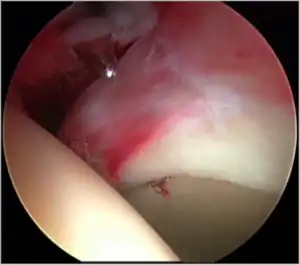

Figure 5. Portal placement under direct vision. The instrument is entering the joint through the hip capsule, between the femoral head (on the left) and acetabular labrum (on the right)

The procedure is performed with the patient asleep (general anaesthetic) or under spinal anaesthesia. There are two widely used methods, one with the patient on their back (supine) and the other on their side (lateral decubitus). Which is used is down to the surgeon's preference. To gain access to the central compartment of the hip joint (between the ball and socket), traction is applied to the affected leg after placing the foot into a special boot. (See fig. 2) There is specifically designed equipment for this, although some surgeons use a 'traction table', initially designed to help in the operative fixation of broken thigh and lower leg bones. The amount of traction (or pull) needed is assessed with the help of fluoroscopy (low-dose portable x-ray). (See fig. 3) It is usually not possible to distract the ball from the socket with traction alone by more than a few millimetres. Once the surgeon is happy that they will be able to gain access to the hip joint (i.e. the ball will distract from the socket by a small amount), the patient is then painted with antiseptic and the surgical drapes applied.

The next step is to insert a fine needle under x-ray guidance into the hip joint. This breaks the 'suction seal' of the joint and allows further distraction if necessary (see fig 4). The surgeon wishes to see the ball move out the socket by approximately 1 cm, so that access to the hip joint can be achieved with minimal risk of damage to the joint surfaces. Most surgeons will inject fluid into the joint at this stage, again to ensure that there is enough space between the ball and socket for safe instrument access. This needle is then removed. The next step is placement of the 'portals', or the small holes made to pass instruments into the joint. This is achieved by again passing a fresh hollow needle into the joint under x-ray control, usually in a slightly different position. The reason for this is so the surgeon can ensure that the needle, and subsequent cannulae do not penetrate and damage the acetabular labrum or cartilage joint surfaces (see fig. 5). Again, surgeons will have their own preferences as to their preferred placement. Through this hollow needle, a long thin flexible guide wire is passed into the joint, and the needle is removed over it, leaving the guide wire in situ. A small cut in the skin is made around the wire, to allow for larger cannulae to be placed over the wire through the portal. The wire therefore guides the larger cannulae into the joint. The most common external diameters of cannulae used are between 4.5 and 5.5 mm. Once the surgeon is satisfied that the cannula is in the correct position, by a combination of feel and x-ray guidance, the guide wire can be withdrawn. Once the first portal is correctly placed, any further portals may be created once the camera is in position, to ensure that they are placed with minimal risk to the joint surfaces. This process can be repeated to gain as many points of entry to the hip joint as the surgeon requires, normally between two and four. Certain of these entry points will be used for the viewing arthroscope and others for operating instruments.